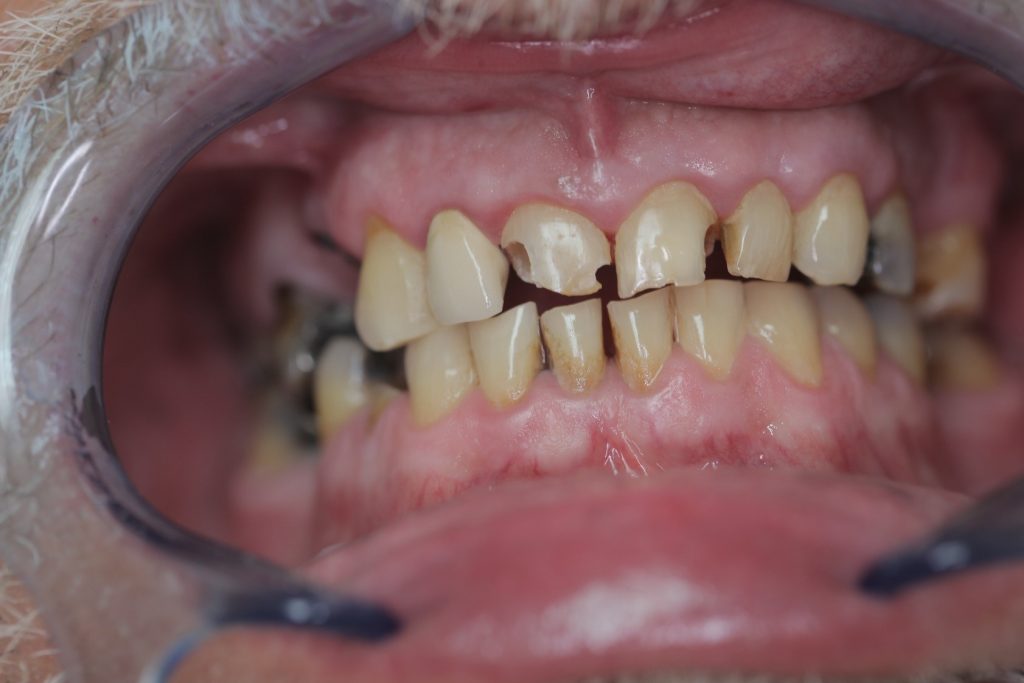

Multiple front teeth fillings, edge restorations using Asteria composite (Case presentation) (54)

A male patient, aged 67, reported to our clinic with the aim of having his condition assessed. He received a detailed treatment plan for his dental problems, which meant the fabrication of a full-arch bridge for his upper jaw. During the patient’s 2-day stint in Hungary we tried to focus on dealing with the most critical problems.

The front teeth were filled using Tokuyama Asteria Estelite filling materials.